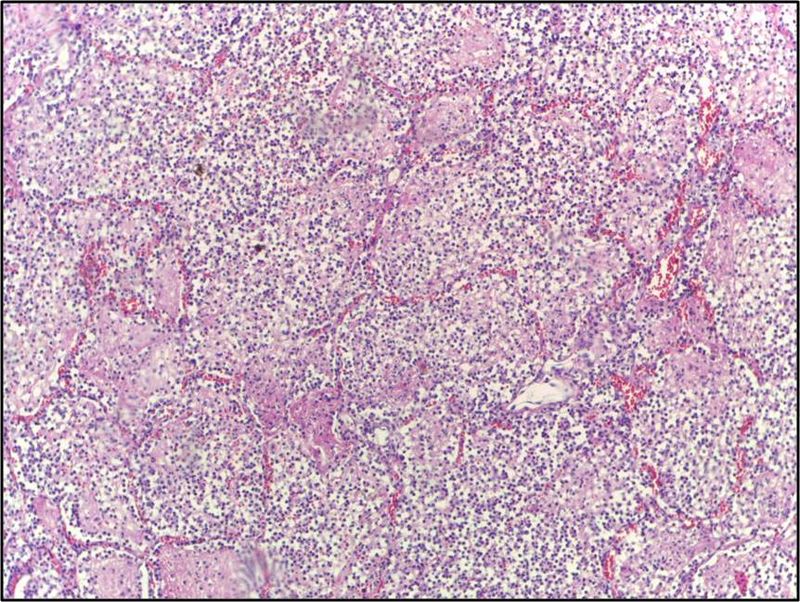

Tuberculosis (TB)

As a result of first-time exposure to aerosolized Mycobacterium tuberculosis, primary tuberculosis (TB) develops.

Tuberculosis (TB) results in the hilar lymph nodes undergoing fibrosis and calcification to produce a Ghon complex as well as localized, caseating necrosis of the lung.

Although primary tuberculosis (TB) usually has no symptoms, it results in a positive purified protein derivative (PPD) test result.

When Mycobacterium tuberculosis reactivates, secondary tuberculosis (TB) develops.

Reactivation of Mycobacterium tuberculosis is frequently caused by AIDS, although it can also be caused other immune compromising issues such as disease or advanced age.

Tuberculosis (TB) usually occurs at the lung’s apex due to the high oxygen tension in that region of the lungs.

Tuberculosis (TB) creates a cavitary foci of caseous necrosis and has the potential to cause tuberculous bronchopneumonia or miliary pulmonary tuberculosis.

Histology of tuberculosis (TB) shows caseating granulomas, and positive acid-fast bacilli (AFB) stain.